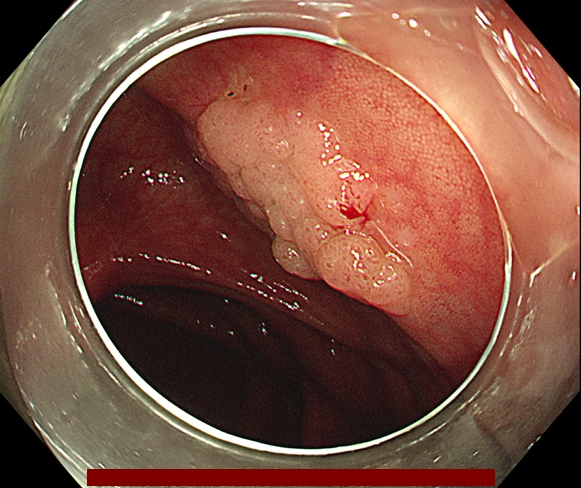

조직 검사 단독으로는 악성 세포의 존재를 배제하거나 악성 세포가 있다는 것을 확증하는데 부적절합니다. 다음 그림과 같이 악성세포가 용종에 존재하지만 조직검사로는 정상 조직을 얻을 수 있기 때문에 용종절제술로 일괄 절제해야 합니다.

오로지 용종을 완전 절제해야만 정확한 조직학적 진단이 가능합니다.

다음은 대장내시경 중 발견된 용종을 일괄 절제한 과정입니다.